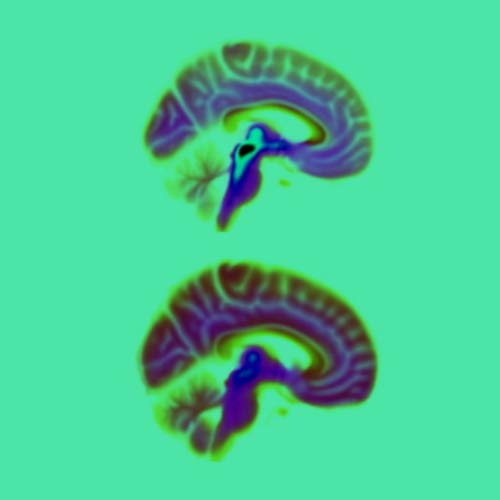

- Een hersenscan maken (gebeurt soms om andere ziektes uit te sluiten).

Pas als iemand overlijdt kun je, tijdens hersenonderzoek onder de microscoop, parkinson met zekerheid vaststellen. Wetenschappers willen dat dit verandert. Zo proberen wetenschappers met nieuwe vormen van MRI of juist met een extra krachtige MRI-scanner te kijken of je de ziekte van Parkinson in de hersenen kunt zien, terwijl iemand nog leeft. Ook onderzoeken ze waarom er zoveel verschillende symptomen zijn. In de toekomst kun je zo de ziekte misschien beter voorspellen. En de behandeling voor ieder mens precies passend maken.